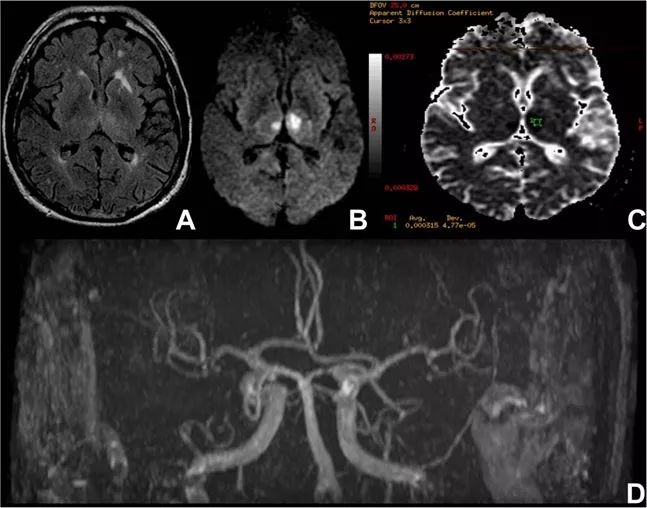

丘脑下外侧动脉又称丘脑膝状体动脉,起源于PCA的P2分支,位于后交通动脉水平之后,由一组小动脉组成,为丘脑下外侧区域供血。

丘脑下外侧动脉的梗死可导致丘脑综合征,最突出的特点是镇痛药不能缓解的剧烈疼痛可能和丘脑与皮层抑制的分离有关。丘脑疼痛多延迟发作,也可立即发作。大约80%该区域梗死的患者存在这种综合征。

该综合征的其他症状还包括感觉丧失和四肢运动障碍。感觉障碍可涉及所有类型的感觉,但不一定全部出现在一名患者中。若患者同时出现感觉丧失和无力偏瘫的症状,则强烈提示丘脑综合征。

此外,患者发生纯感觉综合征(失去所有形式的感觉),特别是当症状累及面部和手臂时,也高度提示该部位的病变。一些纯感觉综合征患者也可能出现迟发性疼痛和/或感觉迟钝。

有学者描述了一种特殊的手部症状,患者的手部弯曲内旋,拇指藏在其他手指之下,被称为丘脑手,也是该部位梗死的特征性表现。目前该部位梗死的患者尚未出现更复杂的行为综合征,偶有语言障碍和失语的报道。

图7 丘脑下外侧动脉供血示意图和梗死影像学表现